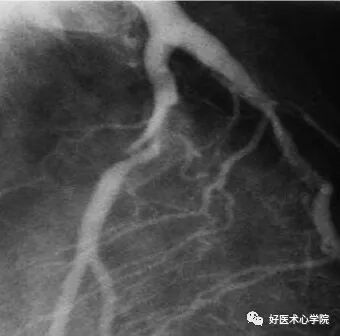

9. 侧支循环(Collateral Circulation)

当冠状动脉严重狭窄或阻塞时,近端灌注压明显下降,刺激侧支循环形成,血管远端被侧支循环逆向供血而显影。

造影导丝是什么珍藏 冠脉造影从流程到诊断,基础必备!_https://www.jmylbn.com_新闻资讯_第96张

侧枝:右冠脉→左前降支